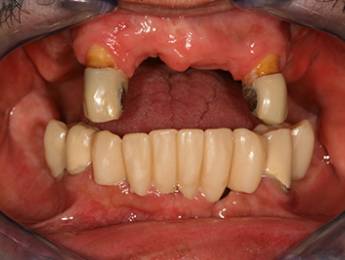

1. eset

A páciens fogágybetegség miatt érkezett hozzánk. A felső fogak menthetetlen állapotban voltak. All on 6 megoldásként a felső fogak eltávolításakor 6 implantátum került beültetésre és a páciens azonnal egy fix ideiglenes hidat kapott. 4 hónapos gyógyulási idő után készült el a felső fémkerámia leplezésű körhíd.